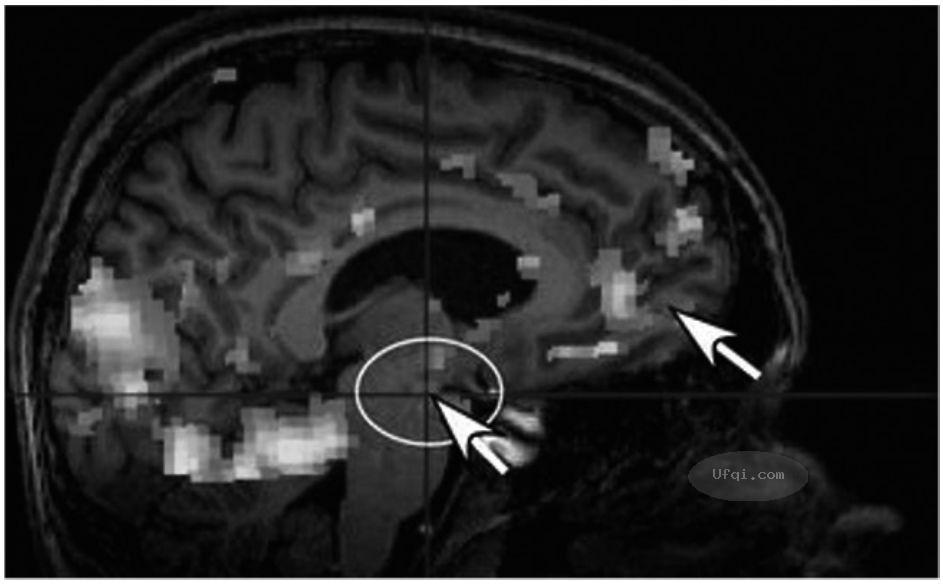

2025-04-01...津巴多普通心理学 Psychology: Core Concepts 4: 第九章: 动机与情绪-15 9.10.4 大脑皮层与边缘系统的连接 现在的神经科学家认为,他们已知道了情绪和理性在大脑中的相遇之处,即有意识的情绪处理途径与边缘系统的连接。这是一小块有着响亮名字的脑区:腹内侧前额皮层(Ventromedial... 171 🈶🖼️

2025-04-01...津巴多普通心理学 Psychology: Core Concepts 4: 第九章: 动机与情绪-14 关键问题:什么过程控制了我们的情绪 核心概念9.5大脑中有两种情绪处理系统:一种是有意识的,另一种是无意识的。这个发现为一些关于情绪与认知的早期争论提供了新的思路。 假设你在万圣节玩鬼屋探险,这时一个电影人物用幽灵... 168 🈶🖼️

2025-02-27...津巴多普通心理学 Psychology: Core Concepts -3: 第八章 意识状态-3 8.1 研究意识的工具 学习目标:描述用于研究意识的技术。 高科技工具,如fMRI、PET和EEG[1],打开了通往大脑的新窗口,使研究人员能够看到在各种不同心理任务中哪些脑区处于活跃状态。换句话说,我们可以辨认出意识中... 172 🈶🖼️